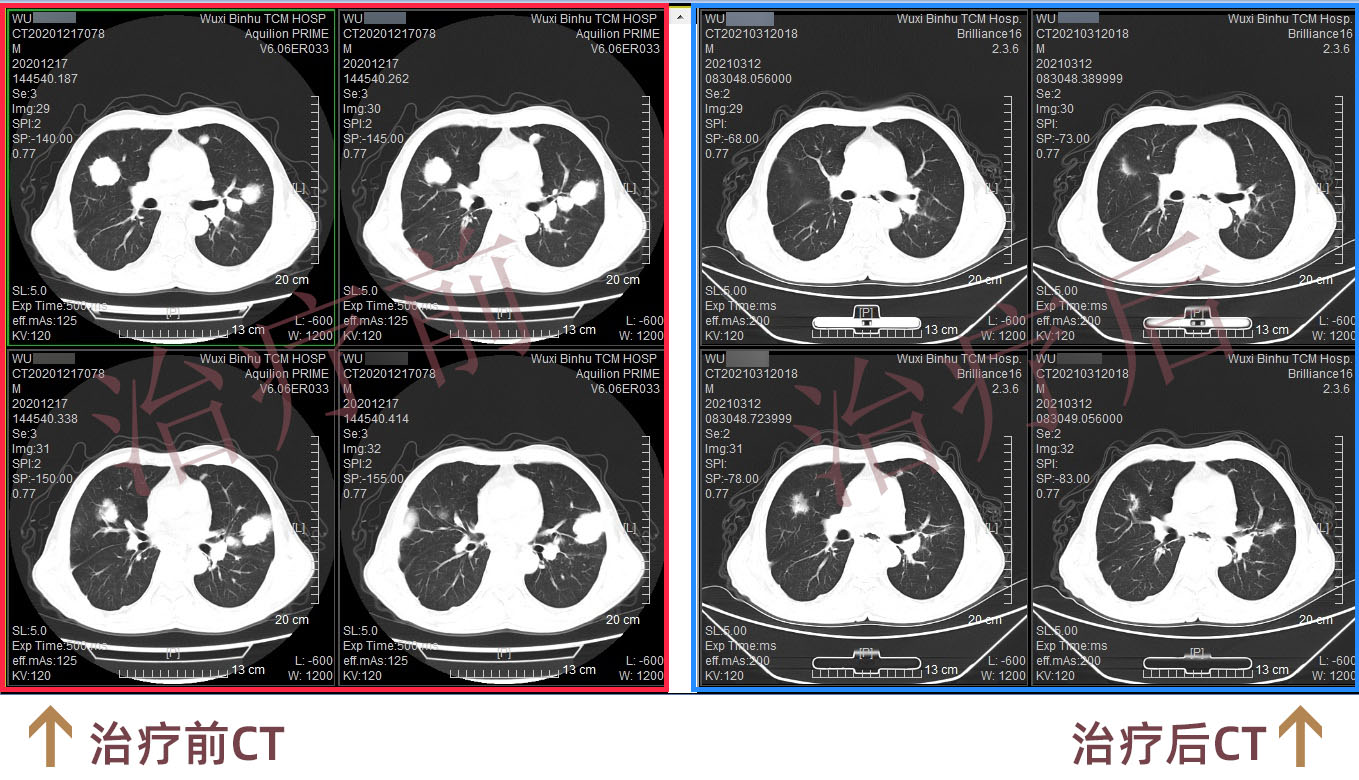

据了解,吴先生1年多前在外院做了胸腔镜中转开放食管拔脱术+空肠造瘘术,术后病理:食管上段中分化鳞状细胞癌,癌组织累及外膜层,脉管内见癌栓,淋巴结见癌转移。术后辅助放化疗期间出现病情进展,两肺、右侧锁骨区及纵隔多发转移,自行口服多种外购靶向药物。定期复查CT提示两肺多发小结节均较前增大(最大径约41mm)。

经过两程治疗后,行CT评估患者两肺转移瘤较前明显缩小,进食梗噎及腹胀症状也得到缓解。